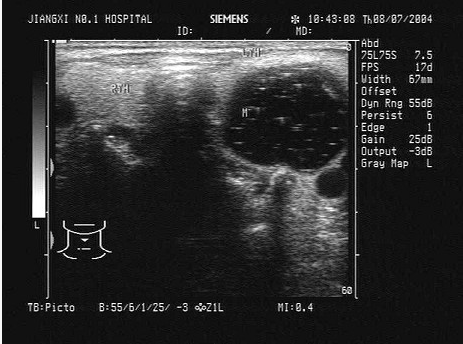

18、单项选择题

临床资料:女,40岁,自诉右侧颈部不适.临床物理检查:右颈部可扪及一肿物,边界清晰,可随吞咽上下移动。超声综合描述:甲状腺右叶中部可见3.0cm×1.4cm不均质回声区,内可见数个强回声光团,最大直径0.4cm,后伴声影,CDFI:不均回声内血供丰富。见下图及彩图。

超声提示()。

A.甲状腺癌(右叶)

B.甲状腺腺瘤合并钙化(右叶)

C.结节性甲状腺肿

D.甲状腺钙化灶(右叶)